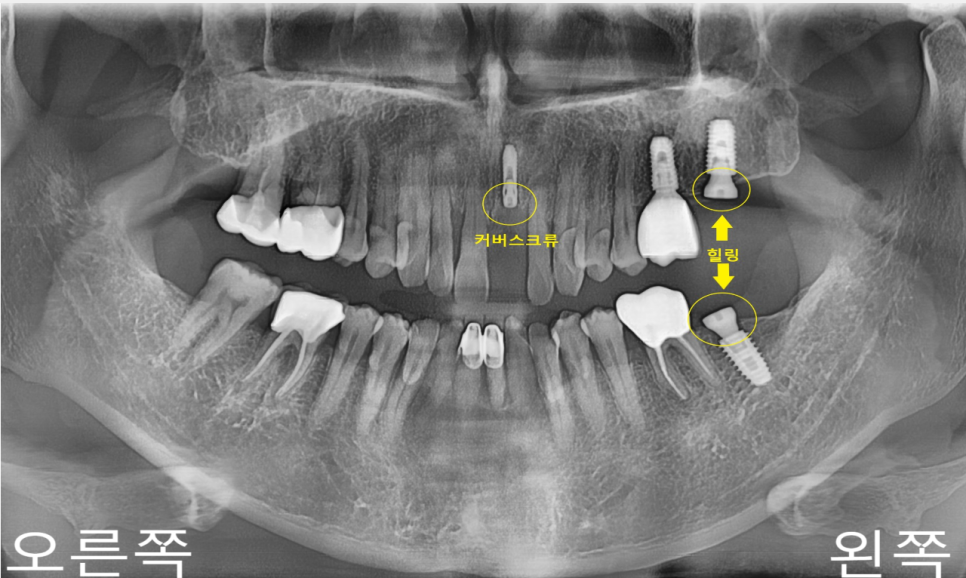

임플란트의 고정상태와

치조골 상태에 따라

커버 스크류와

힐링 어버트먼트 두 가지 종류를

사용하게 되는데

커버 스크류의 경우 잇몸 속에 묻어두게 되어있어.

2차 수술을 하여 잇몸 속에 있는 커버스크류를 제거하고

힐링 어버트먼트를 체결하여

잇몸의 모양을 만들어 줍니다.

2차 수술을 해야 하는 불편함이 있지만

잇몸 속에 있어 고정력을 높일 수 있고

결합을 방해하지 못하게 할 수 있습니다.

*힐링 어버트먼트는

보철물을 올리기 전 치조골과 임플란트 골융합 기간에

잇몸을 회복시키는 구조물로 볼 수 있습니다.

환자분의 경우

중절치는 발즉임플란트를 진행하였고

치조골이 퇴축된 상태여서

커버 스크류로 진행하였습니다.

상하악 좌측 제2대구치의 경우는 발치하신지

시간이 오래되어 치조골은 매우 좋은 상태였습니다.

치조골 상태가 좋은 경우는 바로 힐링 어버트먼트를 사용합니다.